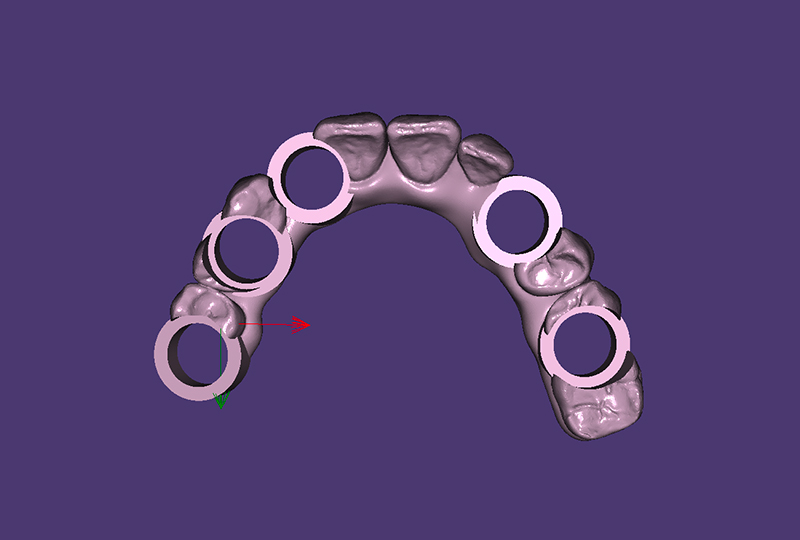

I controlli di verifica lungo il flusso digitale sono permessi dalle procedure di scansione CSS|Strategy, riscansione Re|Scan e validazione De|Bug permessi tramite l’utilizzo del corpo di scansione Scan|Transfer (IPD Dental Group / AbutmentCompatibili.com). La scansione degli ScanBody avviene con una replica forata in prossimità degli impianti della protesi provvisoria (Figura 3). Questa procedura permette di riportare correttamente la posizione degli impianti, la masticazione, la dimensione verticale, la linea mediana e l’estetica per il definitivo (Figura 4).

Il bloccaggio tra protesi forata e Scan|Transfer effettuato con compositi iniettati , eseguito da Diego sul paziente, ottimizza il processo di scansione creando aree facilmente rilevabile dallo scanner intraorale utilizzato, PrimeScan Sirona (Figura 5).

concetto di CSS| Strategy: creare un percorso facilmente leggibile dagli scanner attraverso il collegamento alle teste degli scanbody

La CSS|Strategy, propedeutica alla successiva procedura, prevede la solidarizzazione degli ScanBody/Scan|Transfer con la protesi duplicata e forata, riducendo la scansione intraorale al minimo necessario, da canino a canino, continuando l’acquisizione fuori dal cavo orale senza mantenere il paziente in poltrona, procedura di Re|Scan (Figure 6, 7).